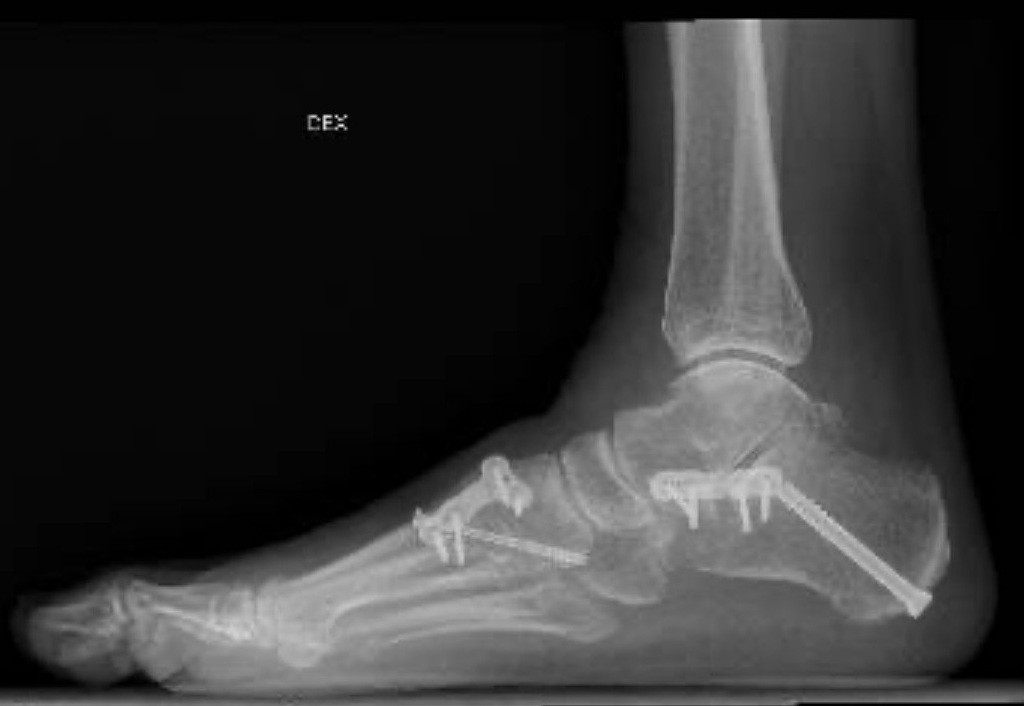

Kuvien mukaan leikkaus oli onnistunut erinomaisesti ja luutuminen oli päässyt hyvin käyntiin. Omaan silmääni pisti ennen-jälkeen kuvien suuri muutos. Maallikkona mielipiteeni on, että kivut johtuvat muutoksesta jalkaterän asennossa. Kivut ovat olleet jalkapöydän päälle liitetyn implantin kohdalla ja sen ympäristössä aina isovarpaan juuresta jalkaholviin asti, jalkaholvi mukaan lukien.

Olin tietysti hyvilläni, että leikkaus oli onnistunut hyvin. Röntgen-kuvia iloisena esitelleelle ortopedille sanoin, että leikkaus siis onnistui, mutta potilas kärsii. Jäin miettimään, olisiko ortopedi voinut muokata jalkaterää vähemmän ja silti saada riittävän hyvän lopputuloksen. Olen ymmärtänyt, että esimerkiksi ensimmäistä tarsometatarsaaliniveltä ei aina luuduteta, kun rakennetaan uusi jalkaholvi. Tämä tehdään vain, jos jalkapöytä on liian liikkuva/löysä. Juuri tämä luudutusimplantti on aiheuttanut pahimmat kivut. Varmaankin se oli silti minun tapauksessani järkevää asentaa. Lisäksi kantapää oli asennettu uudelle paikalleen (kahtia sahauksen jälkeen) lyömällä naula sen läpi ja kiinnittämällä levy sen sivulle. Tämä levy näkyy osittain ao. kuvan alareunassa.